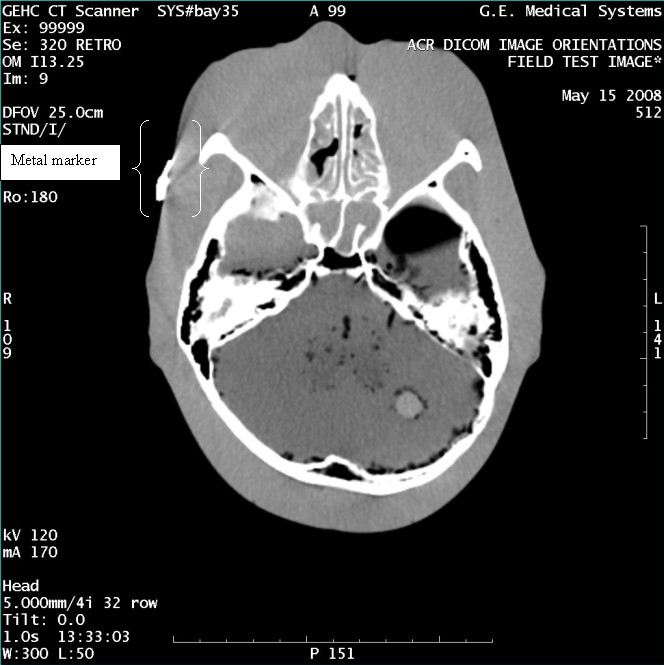

- With the support of the site personnel, examine the images sent

to the Review Station (i.e., 12 series, each with 1 image) and compare

their orientation to the images in this document.

- Each image contains a metal marker on the phantom's right cheek.

- Each image in this document contains a description of the expected

orientation of the metal marker (i.e. to prove Left and Right) as

well as the Posterior and Anterior orientation description.note:

The sample images included in this document use “R”, “L”, “P”, and “A” for “Right”, “Left”, “Posterior” and “Anterior” orientation. The Hospital Review Station may use a different style of annotation. The style used is not relevant to this procedure.

Figure 5. Exam 99999, Series 320